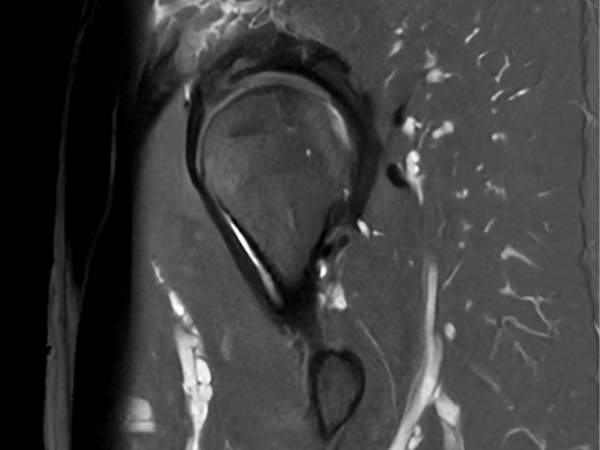

Fast bilateral hips, with SmartSpeed Precise

Used Solution